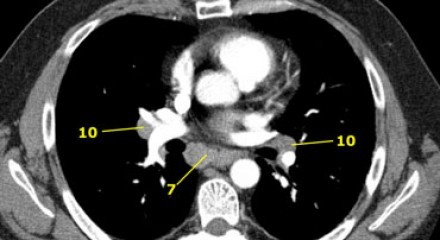

8. Linfonodos Paraesofageanos

Estes linfonodos estão abaixo dos linfonodos carinais e se estendem caudalmente até o diafragma.

.jpg)